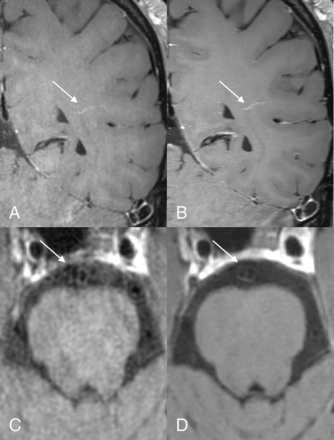

Postcontrast reformatted images in 2 different patients. The upper row shows atherosclerotic involvement in the right A2 ACA segment on the clinical (A) and DLBIR (B) images (arrows). The lower panel, from another patient, shows early atherosclerotic changes in the right V4 segment (arrows). The hypointense wall signal corresponded to underlying calcification on the CT images (not shown) and is better appreciated on the DLBIR image (B).

Upper row images (A and B) from a patient show an incidental developmental venous anomaly in the left temporal region (arrow), equally well seen on the clinical (A) and DLBIR (B) images. Lower row panel (C and D) from another patient with basilar artery fenestration. Image acceleration artifacts in the clinical image (C) almost obscure the underlying fenestration (arrows), which is better seen on the DLBIR images (D).

The current work shows that DLBIR images may not only help improve image quality but can provide considerable time savings, allowing easier and widespread implementation in routine clinical practice. The reduced image noise and consequently improved image quality can potentially improve reader confidence in image interpretation. The savings in gradient times provide further room for adding additional tissue-weightings such as T2WI TOF-MRA, while maintaining overall scan times. Even though we evaluated only a limited number of patients with intracranial lesions, these cases included a diverse array of pathologies, including atherosclerotic disease, cerebral amyloid angiopathy–related inflammation, aneurysm, basilar fenestration, and developmental venous anomaly. In all cases, lesion depiction was similar or better on the DLBIR images. For example, the DLBIR images better depicted the aneurysm wall despite proximity to the cavernous sinus (Fig 2). Similarly, visualization of atherosclerotic disease in the distal ACA was again better with the DLBIR sequence, as was the wall calcification in the V4 segment of the vertebral artery (Fig 3). Finally, the basilar artery fenestration in another patient (Fig 5) could be visualized on the DLBIR images, despite near-complete obscuration on the T1 SPACE images secondary to image noise. In the patient who eventually went on to have a brain biopsy and was shown to have cerebral amyloid angiopathy–related inflammation (Fig 4), the DLBIR images had better image quality despite visualization of the pathology on both sequences.